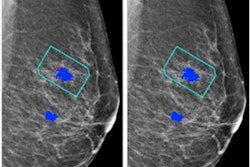

That's how AI can help, Arab Ahmadi said. He and colleagues explored whether an AI algorithm could improve junior radiologists' cancer detection performance via a study that included 2,060 digital mammography exams from 515 women taken between 2018 and 2022. Of these exams, 240 showed malignancies and 1,820 were benign. Four junior radiologists reviewed and interpreted the exams without assistance from the AI algorithm and then were presented with AI-generated interpretations of the same exams and given the opportunity to revise their interpretations. Arab Ahmadi's group compared radiologist performance before and after AI assistance, tracking measures such as the area under the receiver operating curve (AUC), sensitivity, and specificity.

The AI technology improved the AUC and sensitivity of the junior radiologists' reading performance, helping them identify previously missed masses, calcifications, distortions, and asymmetries.

"[AI-boosted readers' sensitivity] while keeping specificity acceptable, which is the most important in the screening phase," Arab Ahmadi concluded.